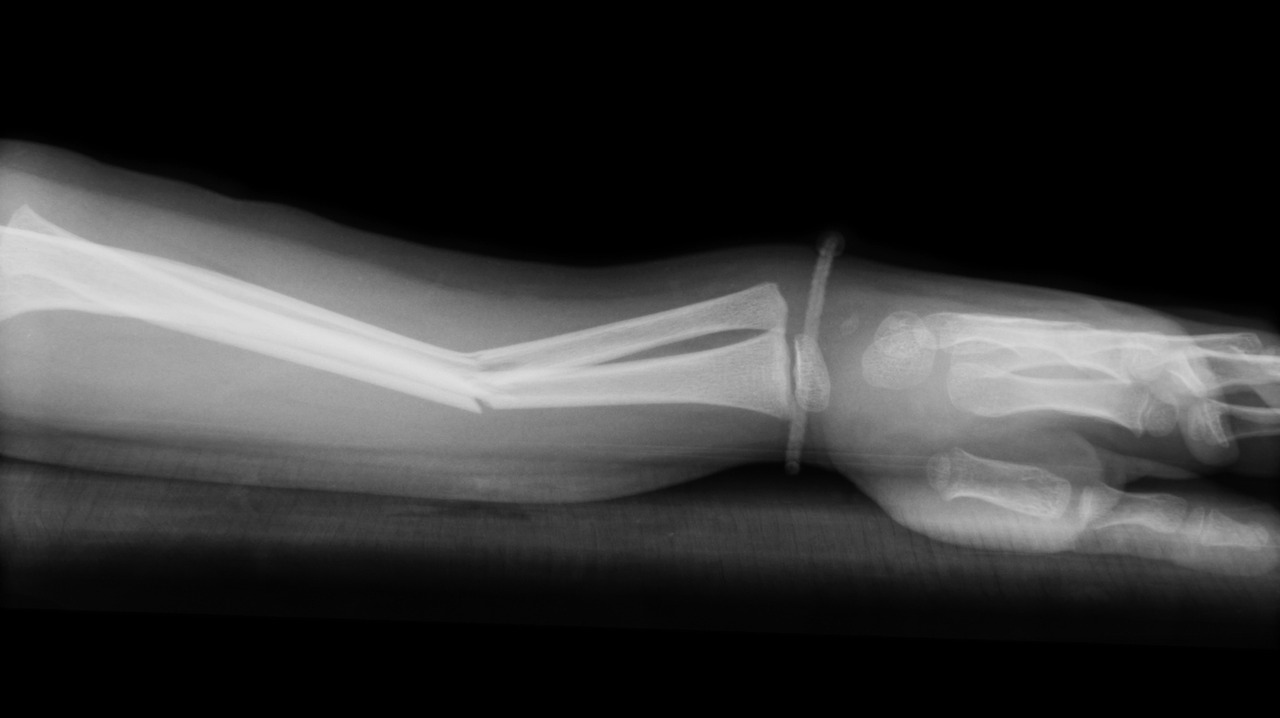

대표적인 운동 중 골절의 예

상대 선수 혹은 기물과의 접촉이나 과격한 움직임이 요구되는 경기나 훈련에 참여하는 운동선수에게 골절의 위험성은 대단히 크다. 운동 중 골절의 경우 작고 얇은 손과 손목, 발과 발목 부위 뼈들의 골절이 대부분이지만, 과도한 외력(충격)에 의한 크고 굵은 다리나 팔, 혹은 척추 뼈의 골절 가능성 역시 높다.

상대적으로 커다란 뼈들의 골절 시에는 해당 뼈의 골절 이외에도 2차적으로 근육이나 혈관 또는 신경의 손상을 야기할 수 있기 때문에 더욱 세심한 부상 점검과 적절한 응급처치 및 관리가 중요하다.

의식의 소실이나 호흡 곤란 혹은 내장의 손상을 초래할 수 있는 머리와 흉부의 골절, 신경적인 손상이 동반될 수 있는 척추 골절, 그리고 주요 혈관의 손상으로 인한 과다 출혈의 위험성이 큰 허벅지(긴 다리뼈) 골절 등의 경우에는 상황 발생 즉시 119에 신고하고, 전문 응급 구조사의 도착 시까지 해당 선수의 심리적 안정환부의 보호 및 지혈, 그리고 호흡 유지 등의 노력을 병행 실시해야 함을 명심해두자.